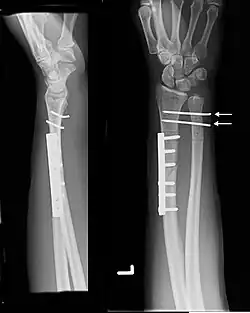

Galeazzi fracture

| Galeazzi fracture-dislocation | |

| Galeazzi fracture. Arrow points at the dislocated ulnar head | |

The Galeazzi fracture is a fracture of the distal third of the radius with dislocation of the distal radioulnar joint. It classically involves an isolated fracture of the junction of the distal third and middle third of the radius with associated subluxation or dislocation of the distal radio-ulnar joint; the injury disrupts the forearm axis joint.[1]

Galeazzi fractures are best treated with open reduction of the radius and the distal radio-ulnar joint.[3] It has been called the "fracture of necessity," because it necessitates open surgical treatment in the adult.[4] Nonsurgical treatment results in persistent or recurrent dislocations of the distal ulna.[1] However, in skeletally immature patients such as children, the fracture is typically treated with closed reduction.[1]